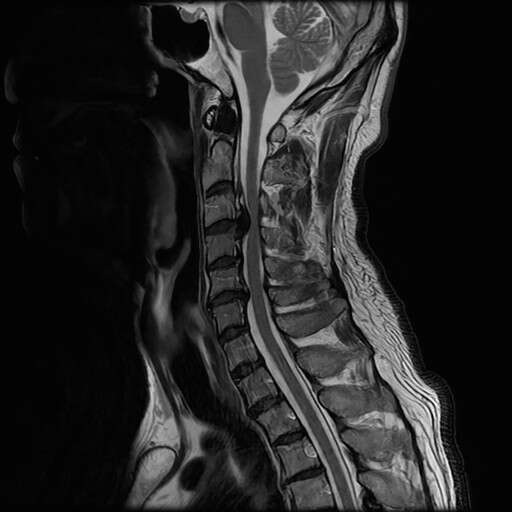

脊椎

脊椎疾患の描出に優れています。